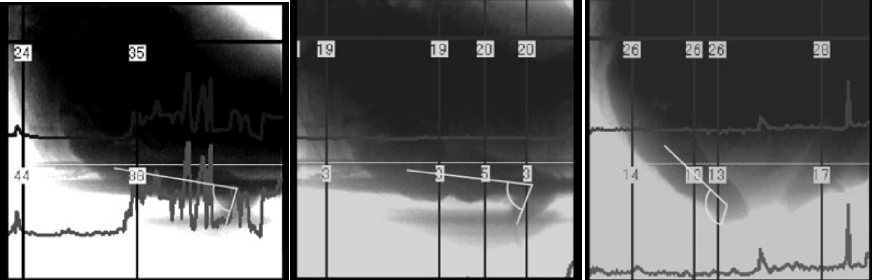

從左到右依次為坐姿、坐姿踩小板凳、蹲姿的直腸-肛門角,圖片來源:參考文獻2

2010 年發(fā)表在《下尿路癥狀》(Lower Urinary Tract Symptoms)上的一項研究,就找來了 6 名志愿者,研究了他們在 3 種拉便便姿態(tài)下的直腸-肛門角,這三種姿態(tài)分別是坐姿、坐姿外加腳踩小板凳、蹲姿。

結(jié)果發(fā)現(xiàn),不同姿態(tài)下直腸-肛門角度之間確實存在差異。

坐在馬桶上,直腸-肛門角的平均度數(shù)為 100°,坐在馬桶上踩著小板凳,平均度數(shù)為 99°,而在蹲姿狀態(tài)下,這一度數(shù)平均值是 120°。所以,在這三種拉便便姿態(tài)下,蹲坑的姿態(tài)確實能夠讓“便便的通道”更順暢。

為了更進一步研究三種姿態(tài)對拉便便的影響,研究者往實驗者的直腸里注入了造影劑,讓他們以三種不同的姿態(tài)進行模擬排便,并且記錄這些姿態(tài)下腹部的壓力。

結(jié)果發(fā)現(xiàn),在三種姿態(tài)下,坐姿狀態(tài)下實驗者需要額外施加的腹部壓力最大,其次為坐姿踩著小板凳,在蹲姿狀態(tài)下實驗者需要額外施加的力最小。

但是在這項研究中,實驗樣本量很?。ㄖ挥?6 個受試者)。而且仔細(xì)看這六名受試者的數(shù)據(jù)也會發(fā)現(xiàn),不同的受試者踩小板凳的情況也有不同。有些人踩小板凳之后直腸-肛門角變大了,確實會讓拉便便更順暢。但有些人這個角度變小了,意味著拉便便反而會受到阻礙。

不踩小板凳與踩小板凳,直腸-肛門角變化,圖片來源:參考文獻2